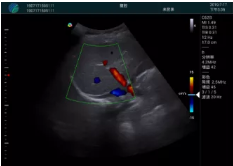

可視化甲狀腺穿刺引導(dǎo)

頸動(dòng)脈血流充盈飽滿,無外溢

肝內(nèi)血管顯示清晰,血流敏感無外溢

病例二:

甲狀腺囊性結(jié)節(jié),囊壁鈣化,透聲好

甲狀腺囊性占位

2001年美國(guó)健康護(hù)理研究和質(zhì)量監(jiān)督局(AHRQ)批準(zhǔn)了一項(xiàng)關(guān)于提高患者安全性的報(bào)告,建議:在頸內(nèi)靜脈中心置管術(shù)時(shí)使用超聲引導(dǎo)。此后超聲引導(dǎo)穿刺被用于幾乎所有的急診穿刺操作,尤其是血管穿刺。

便攜超聲在急診穿刺中的應(yīng)用:

* 提高了穿刺成功率

* 減少了穿刺損傷及并發(fā)癥

* 縮短了操作時(shí)間

* 減輕了患者痛苦